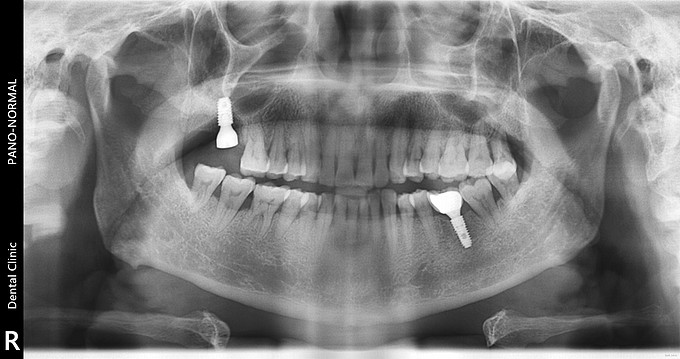

右上后牙缺失种植

右上七牙周炎拔除半年,现种植修复。 缺牙间隙宽 牙槽嵴窄 (牙合)龈距离正常 对合无伸长 邻牙无移位

右上后牙缺失种植修复